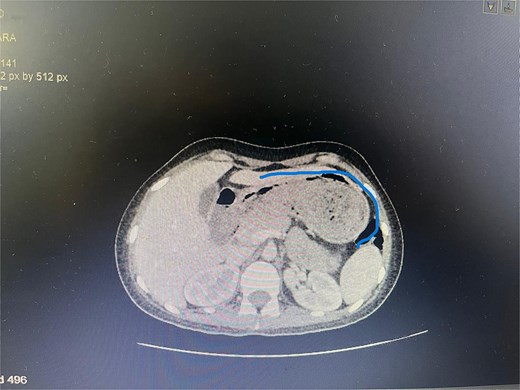

Axial CT image showing the foreign body completely occupying the gastric lumen.